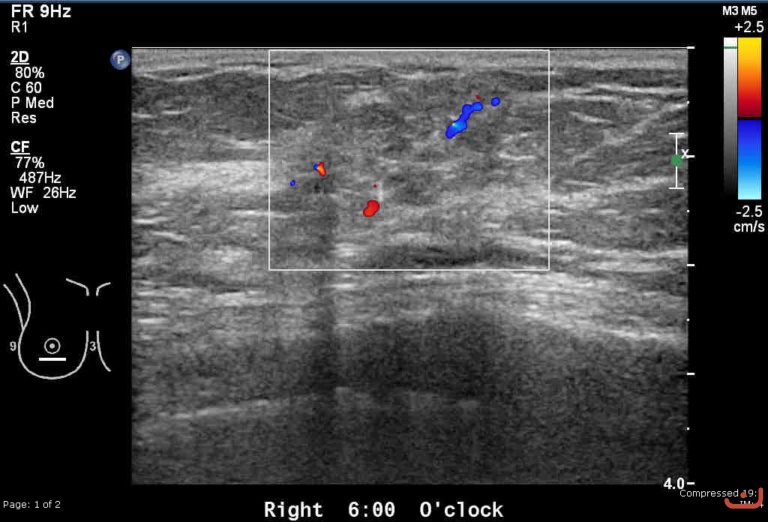

Malignant solid mass

Friday, 22 May 2015

215.45 KB (768 x 522 px)